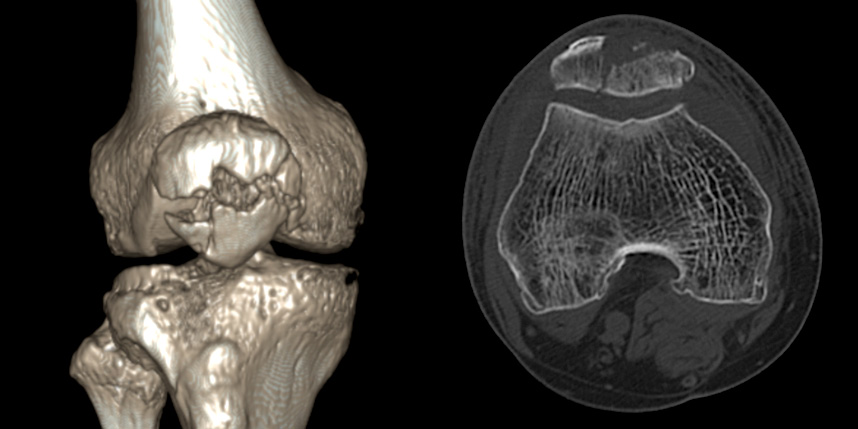

골절은 정확하게 골절편을 잘 맞추고 고정하는 것이 중요합니다. 특히 관절면을 잘 맞추는 것이 중요합니다.

무릎 골절